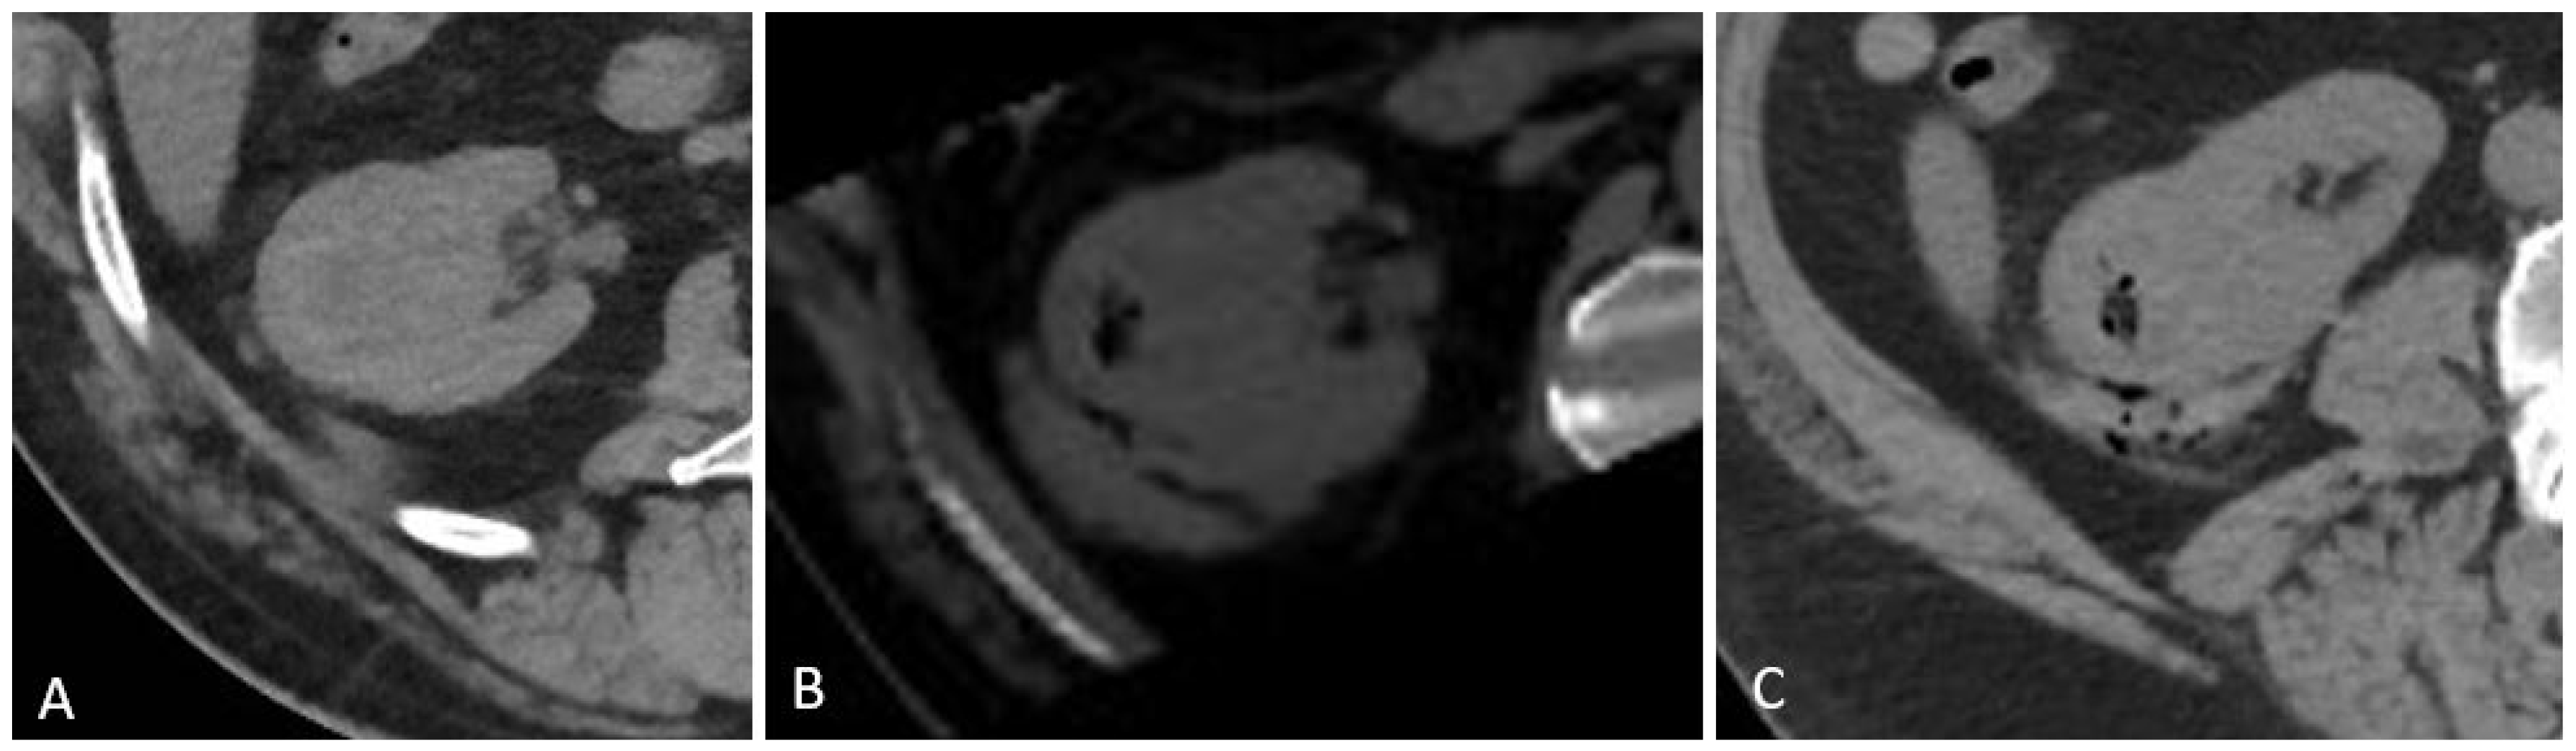

2.3. Biopsy Procedure

2.3.1. Gelfoam Preparation and Injection

2.3.2. Imaging and Post-Procedure Monitoring